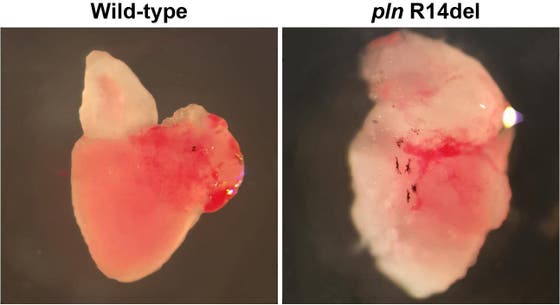

Read moreFirst patient-specific zebrafish model for arrhythmogenic cardiomyopathy

The research groups of Jeroen Bakkers and Toon van Veen bring forward the first patient-specific model for the heart disease arrhythmogenic cardiomyopathy (ACM). They were able to recapitulate the human form of this disease by introducing a genetic mutation called Phospholamban (PLN) p.Arg14del in zebrafish. The cellular changes resulting from the mutation could be recovered using the drug istaroxime. Eventually, the findings – published on 9 December in Nature Communications – may contribute to the understanding of the molecular mechanisms of the PLN mutation and the ways in which the symptoms of ACM can be relieved in patients.